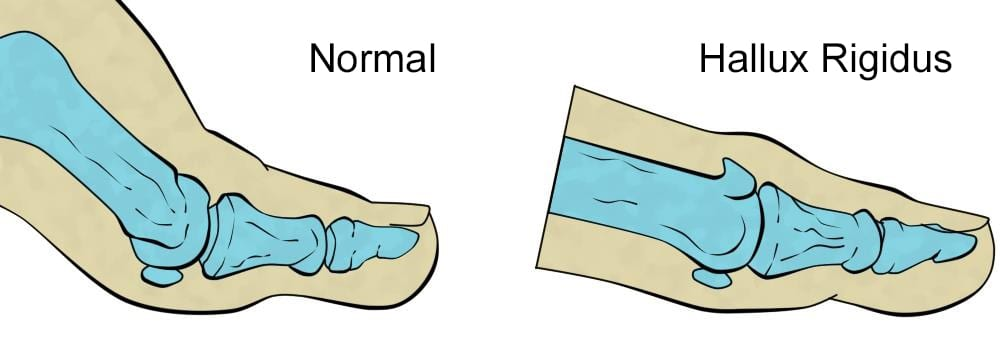

خلاصه این مقاله: آرتروز شست پا یا هالوکس ریجیدوس (Hallux Rigidus) تخریب غضروف مفصل شست است که باعث درد و سفتی شست پا میشود. این بیماری در مراحل اولیه با کفش طبی و تزریق قابل کنترل است، اما در مراحل پیشرفته برای حفظ توانایی راه رفتن، جراحی توسط متخصص ضروری خواهد بود.

آرتروز شست پا چیست و چرا ایجاد میشود؟

آرتروز شست پا یا هالوکس ریجیدوس، فرسایش مفصلی است که در پایه انگشت شست (مفصل MTP) رخ میدهد.

علت اصلی ایجاد آرتروز مچ پا، فشارهای مکرر به مفصل، ناهنجاریهای ساختاری پا (مثل بلند بودن استخوان متاتارس) یا آسیبهای قدیمی (مانند ضربه در فوتبال) است که باعث سایش غضروف و تشکیل استخوانهای اضافه (خار) میشود.